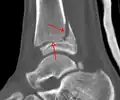

A triplane fracture of the ankle as seen on CT -

CT

CT scans may be indicated when there is concern for a highly comminuted fracture or a fracture involving the joint surface.[10] This imaging may be used for surgical planning.